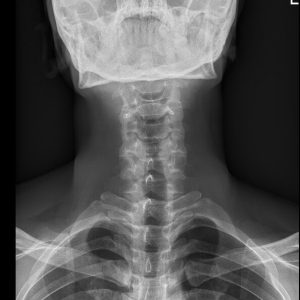

C spine AP view

C spine Lat view